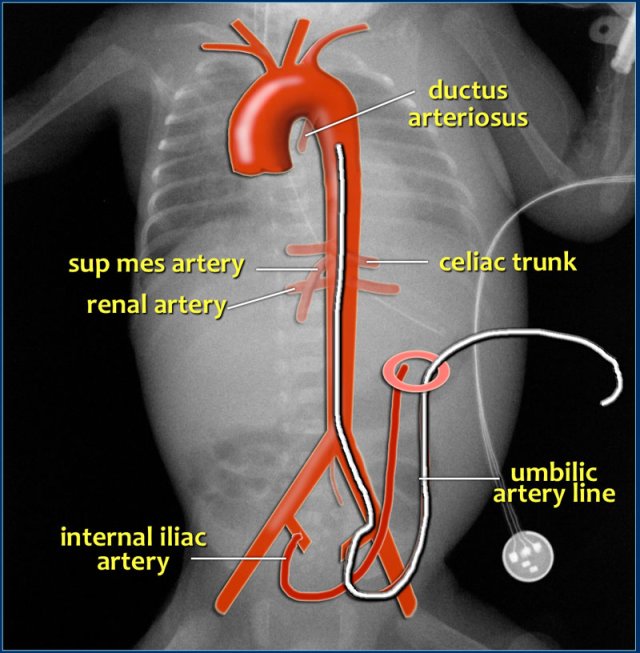

Umbilical artery line

Umbilical artery catheterization provides direct access to the arterial system and allows accurate measurement of arterial blood pressure, blood sampling and intravascular access for fluids and medications.

The catheter should be passed through the umbilic artery and enter the aorta via the internal iliac artery.

It should demonstrate the typical loop from the umbilicus inferiorly into the internal iliac artery.

In order to avoid placement into aortic branches, the catheter should be either in a high position above the celiac, mesenteric and renal arteries or in a low position below the inferior mesenteric artery:

• high position: T6-T9

• low position: L3-L5

The high position is advisable since it leads to less vascular complications (15).